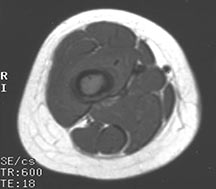

- Radiographically variable appearance: may appear benign (geographic) or malignant (permeative or moth eaten)

Radiographic Presentation